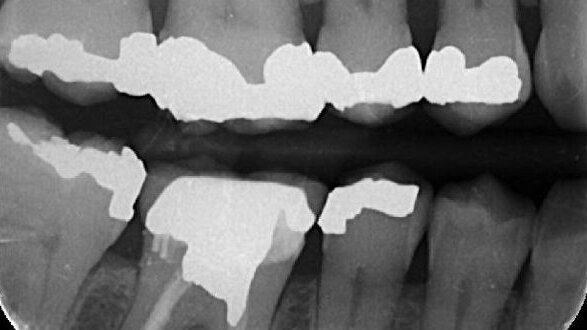

A 58-year-old female patient presented for endodontic evaluation and therapy in the upper left quadrant. Mild pain for several days was reported by the patient prior to the appointment. Medical history was non-contributory, and dental history was remarkable for multiple existing large amalgam restorations (Figs. 1–3). Clinical examination and diagnostic evaluation were performed for all posterior teeth on the right side, including cold testing, percussion, palpation, periodontal probing and bite challenge. Findings led to a preoperative diagnosis of irreversible pulpitis in tooth #3 with normal peri-radicular tissues.

Once the orifice location had been determined, canal negotiation and instrumentation were completed. Warm vertical compaction of gutta-percha and ZOE sealer was used in this case, demonstrating the treated canal morphology (Figs. 7 & 8). The MB2 canal was addressed as a completely separate canal.